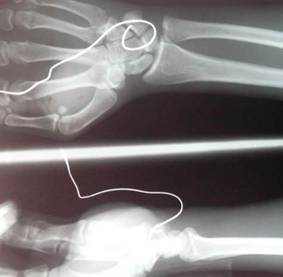

Al llegar al mencionado centro hospitalario se comprobó lo descrito y mediante los estudios radiográficos se observó que alrededor de 10 cm del alambrón se encontraba dentro de las estructuras de la muñeca, doblado en forma de gancho en la parte distal (Fig.2.).

Durante el acto quirúrgico se observó la lesión del tendón del músculo palmar mayor y del nervio mediano en la muñeca. Se retiró el alambrón en sentido contrario a su curvatura y gancho (Fig.3.) y se realizó la limpieza de la zona afectada. Como medida profiláctica se aplicaron 2 g de cefazolina y luego se suturó la piel.